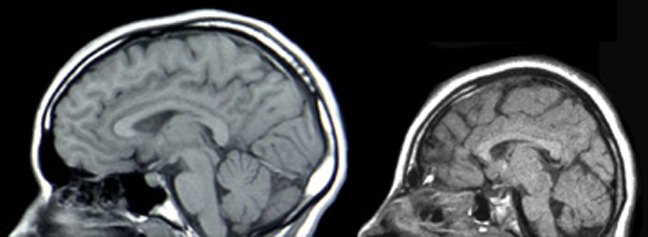

MRIs of a healthy individual (left) and a patient with microcephaly (right). Credit: PLoS Biol 2(5): e134

Well, sometimes they don’t. For about 25,000 babies born in the U.S. each year, the brain doesn’t grow the way it should, leading to microcephaly, a disorder characterized by an abnormally small head (micro=small; cephaly=head). These babies have a range of symptoms including speech delays, seizures, mental retardation and balance difficulties.